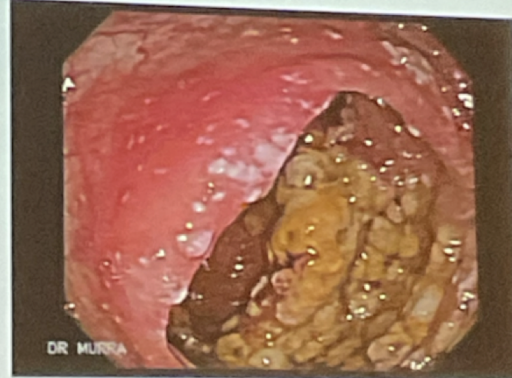

qué enfermedades causa el c. diff?

diarrea y enterocolitis